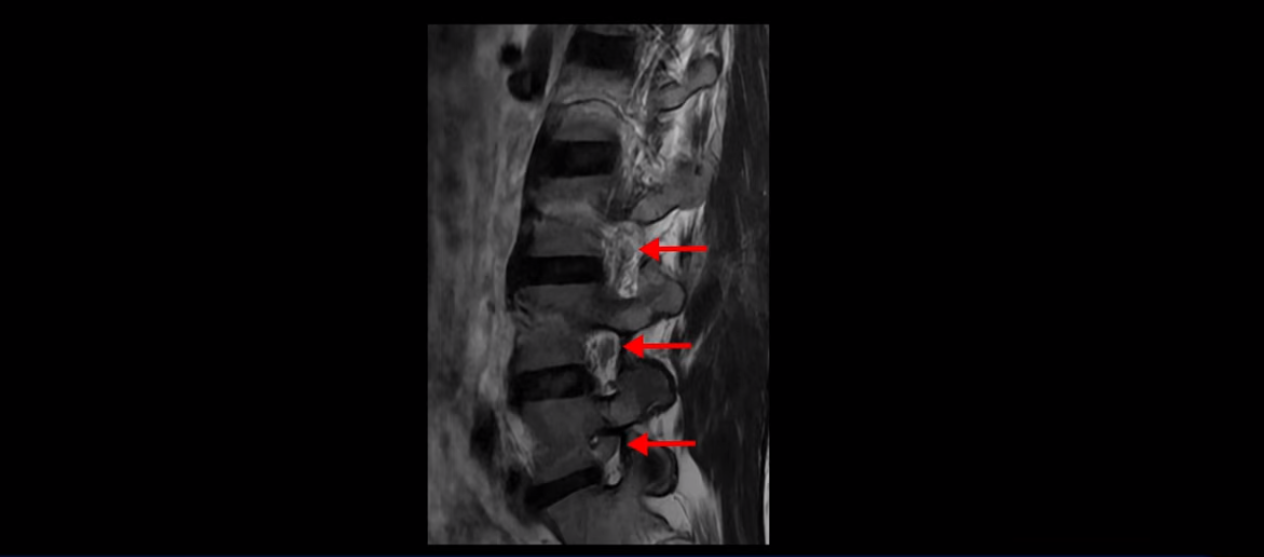

우선 이분 허리 MRI를 보면 5번 1번에 퇴행성 디스크가 있지만 방사통을 일으킬 만큼 신경을 누르고 있어 보이지 않습니다.

오른쪽으로 디스크가 약간 찢어져 보이는데, 작년에 찍은 MRI에서도 보이는 것이라 오래 전에 찢어진 후 아문 흔적으로 보입니다.

중요한 것은 오른쪽 다리에 심한 방사통이 있다든가 재채기를 못 한다거나 허리를 구부리거나 몸을 살짝 비틀 때 날카로운 통증이 없습니다. 즉, 섬유륜이 최근에 찢어진 게 아닌 겁니다.

4번 5번과 3번 4번 마디도 디스크가 중앙으로 살짝 밀려나와있지만 최근에 섬유륜이 찢어진 것도 아니고, 신경 다발을 누를 정도로 심하게 밀려나와 있는 것도 전혀 아닙니다.

양쪽 신경 가지가 빠져나가는 추간공도 충분히 넓어서 신경학적 방사통을 일으킬 여지가 없습니다.

그럼 이 환자분의 양쪽 다리 저림과 발 저림 그리고 앉기만 하면 5분 내로 심한 허리 통증, 엉덩이 통증이 발생하는 원인은 뭘까요? 저희가 이런 디스크 내장증 얘기를 들으신 환자분들 치료 후기에서 수없이 설명하지만, 이런 증상이 디스크가 원인이 아닙니다. 이분도 여러 병원에서 증상과 MRI가 일치하지 않는다고 들으셨는데요.

이 환자분의 진짜 통증의 원인은 허리의 기능이 완전히 무너진 겁니다. 허리의 기능 중에 가장 중요한 부분을 차지하는 게 근육인데, 이분의 근육 기능에는 오래전부터 문제가 많았습니다. 이분은 작년에 앉지 못하고 양쪽 다리가 저리는 심각한 증상이 발생했는데요. 그런데 이런 증상이 발생하기 훨씬 오래부터 일상 생활 중 조금만 무리해도 허리가 뻐근하고 아픈 증상들이 있었습니다. 아주 오랜 시간 동안 허리가 조금씩 아프고 만성적으로 안 좋은 상태였는데, 그게 누적되면서 약 1년 전 어느 날 집안일을 한 후에 허리와 근육의 기능적인 문제가 한계선을 넘어가니까 더 심한 증상들이 쏟아져 나오는 거죠